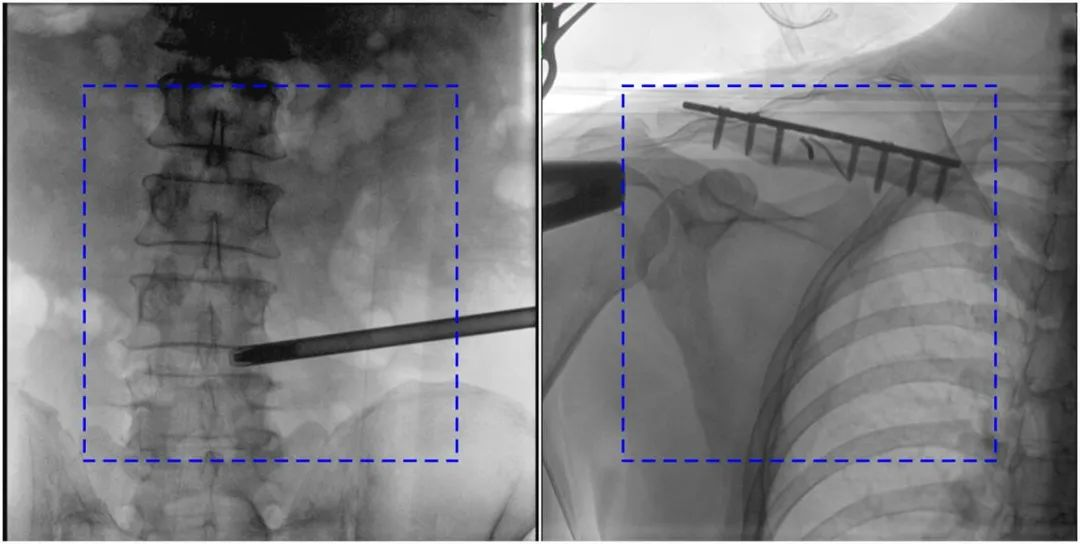

與傳統(tǒng)的21CM×21CM成像尺寸相比,普愛醫(yī)療大平板一體式C形臂具有30CM×30CM更大成像尺寸,能夠一次成像5.5節(jié)椎體,呈現(xiàn)更全面的影像信息,即便是手術(shù)經(jīng)驗(yàn)不豐富的年輕醫(yī)生也能通過圖像迅速判斷椎體節(jié)段、定位手術(shù)部位,避免因?yàn)橐曇安蛔愣斐傻亩啻味ㄎ?、反?fù)曝光,提高效率的同時(shí)避免過量攝入輻射。

普愛醫(yī)療大平板一體式C形臂圖像與傳統(tǒng)圖像對(duì)比(藍(lán)色虛線內(nèi)為傳統(tǒng)21CM×21CM平板的成像區(qū)域)